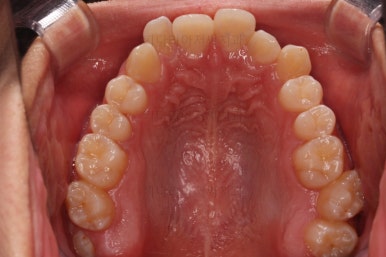

초진 시 입안의 모습입니다.

앞니가 많이 삐뚤고, 송곳니가 부각되어 덧니처럼 보이네요.

종료 시의 사진들을 전후 비교해 보겠습니다.

입매가 좋아졌고 입을 다무는 편안함도 좋아졌으며 치열이 가지런해졌으며 웃을 때 보이는 치열의 느낌도 좋고 교합도 잘 마무리 되었네요.